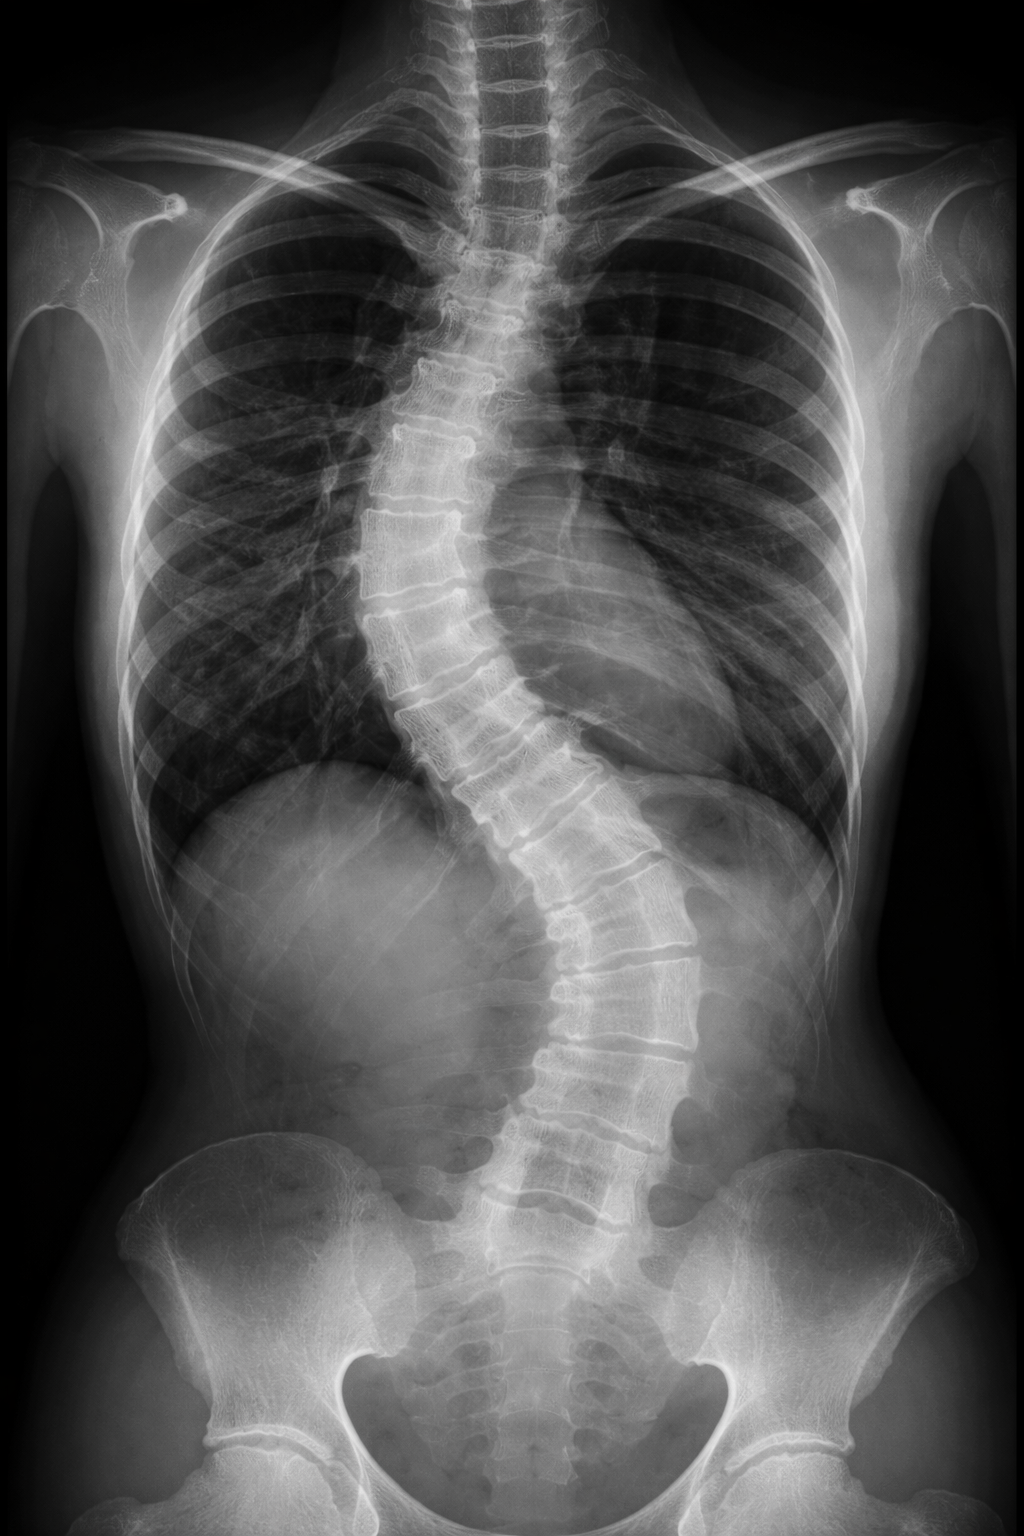

• Detailed Physical Examination: This includes spinal assessment, posture analysis, range of motion testing, and measurement of spinal curves.